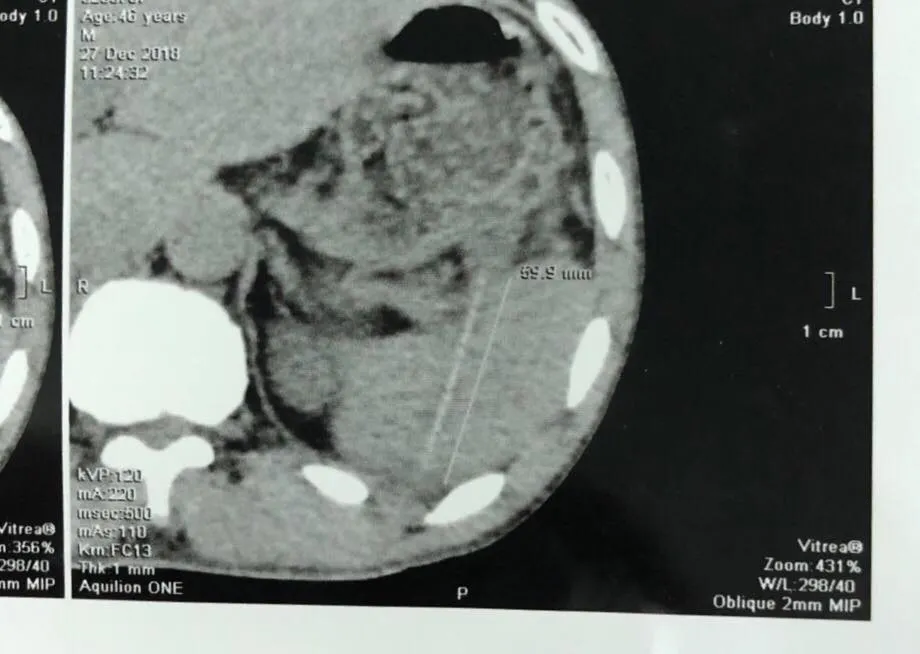

Hình ảnh cây tăm qua CT Scanner. Ảnh: CN

Ngày 23-1, tin từ BV Bình Dân (TP.HCM) cho biết Khoa ngoại Gan-Mật-Tụy của BV vừa phẫu thuật nội soi ổ bụng lấy dị vật là một chiếc tăm dài 6cm, hai đầu vót nhọn khỏi lá lách của một người đàn ông 46 tuổi tên H.

Sau gần hai giờ đồng hồ nỗ lực tìm kiếm cẩn thận vì lá lách vốn là một nội tạng chứa đầy máu, chỉ cần sơ sẩy là có nguy cơ xuất huyết ồ ạt phải chuyển mổ mở, cuối cùng các bác sĩ đã rút được dị vật là cây tăm xỉa răng dài 6cm. Ngay tại thời điểm rút được cây tăm, dịch mủ đục vốn do cơ thể phản ứng với dị vật đã trào ra, đây cũng là một trong các lý do khiến anh H. đau âm ỉ liên tục hai tuần.